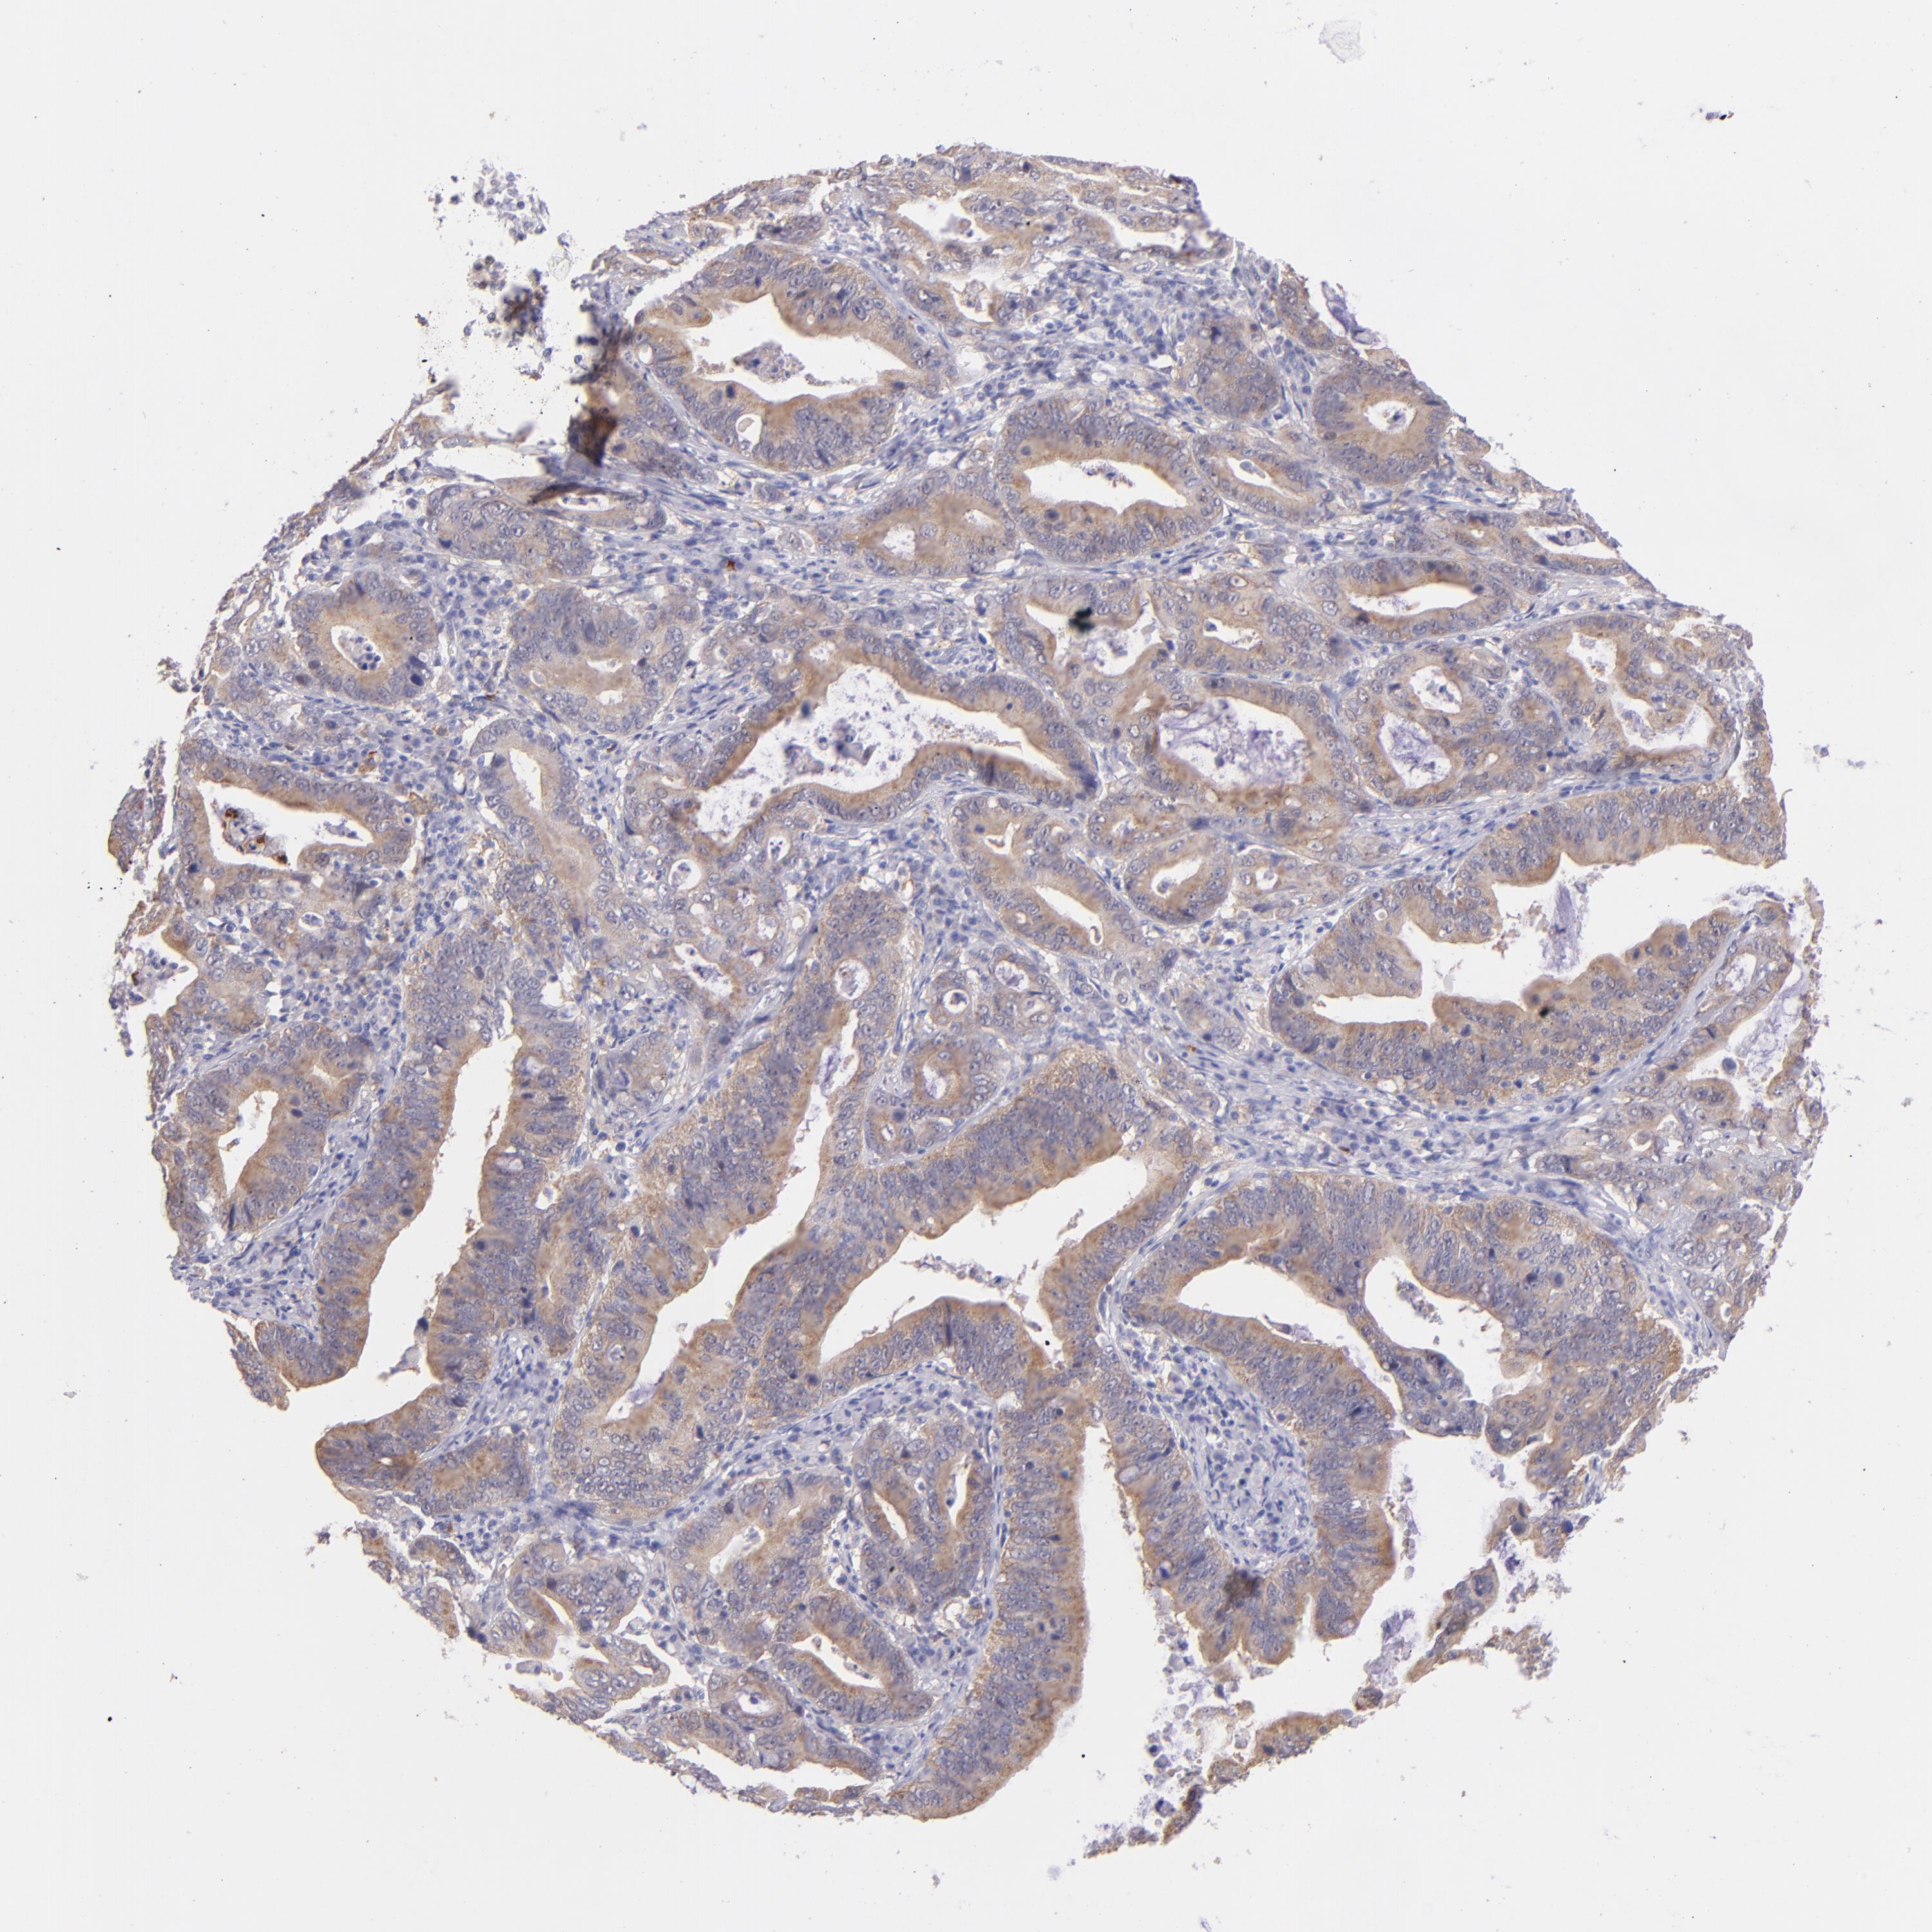

STOMACH CANCER - Protein expressioni

A mouse-over function shows sample information and annotation data. Click on an image to view it in a full screen mode. Samples can be filtered based on level of antibody staining by selecting one or several of the following categories: high, medium, low and not detected. The assay and annotation is described here.

Note that samples used for immunohistochemistry by the Human Protein Atlas do not correspond to samples in the TCGA dataset.

Antibody stainingi

Antibody staining in the annotated cell types in the current human tissue is reported as not detected, low, medium, or high, based on conventional immunohistochemistry profiling in selected tissues. This score is based on the combination of the staining intensity and fraction of stained cells.

Each image is clickable and will lead to virtual microscopy that enables deeper exploration of all samples and also displays staining intensity scores, fraction scores and subcellular localization as well as patient and tissue information for each sample.

Antibody HPA001871

Antibody HPA001919

Staining

High

Medium

Low

Not detected

Intensity

Strong

Moderate

Weak

Negative

Quantity

>75%

75%-25%

<25%

None

Location

Nuclear

Cytoplasmic/membranous

Cytoplasmic/membranous,nuclear

Adenocarcinoma, NOS